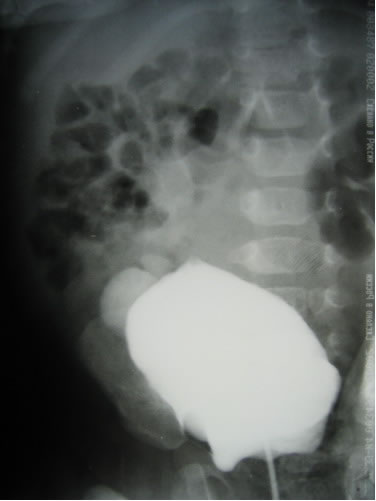

Цистография

С целью определения функционального состояния правой почки

больному было произведено дренирование лоханки правой почки

методом чрескожной пункционной нефростомии. В дальнейшем

ребенок наблюдался амбулаторно. По нефростомическому дренажу

справа выделялось до 300 мл мочи в день. Ребенок поступил

23.10.2006 года для контрольного обследования и определения

тактики лечения